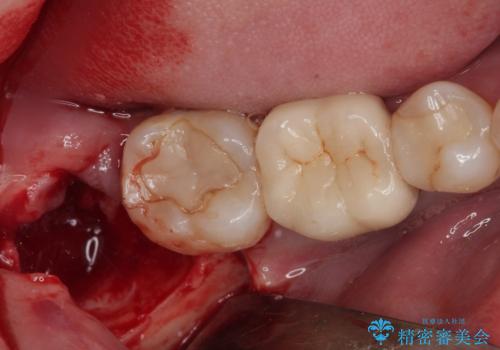

- 右下の親知らずを抜きたいとのことで来院された患者様です。

CTで神経の位置などを確認し、抜歯術を行いました。

しっかり麻酔が効いたことを確認してから安全に抜歯を行いました。